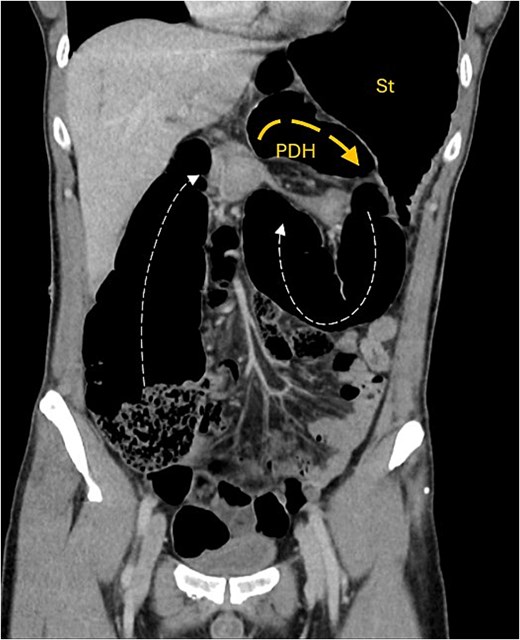

A contrast-enhanced computed tomography (CT) scan of the abdomen and pelvis demonstrated a large bowel obstruction with a transition point at the distal transverse colon with swirling of the mesentery. Downstream large bowel was collapsed. Upstream dilatation included the terminal ileum suggested an incompetent ileo-caecal valve. The gastric antrum was also involved in the internal hernia, resulting in gastric outlet obstruction. See Figs 1–5.

Coronal CT image showing obstructed transverse colon (Tx) path (small dash arrow), looping posteriorly through narrow hernia neck into anterior PDH containing Tx colon segment (wide dash arrow). Stomach (st) is distended.